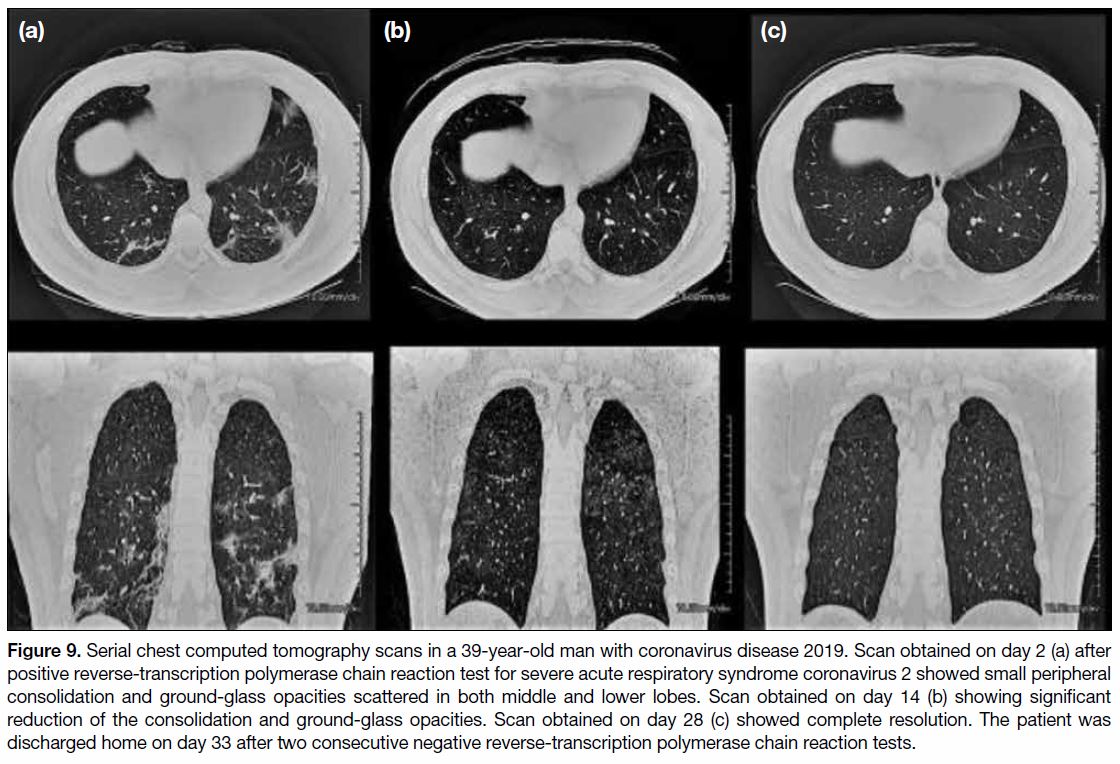

As stated above, not all patients with COVID-19

will undergo follow-up CT imaging. A single-centre

review on the features of follow-up chest CT imaging

revealed that among 70 patients who had chest CT scan

after confirmation of SARS-CoV-2 infection, and

15 patients had a second chest CT scan. The mean

(±standard deviation) interval of the second chest CT

after the first positive RT-PCR test was 21.9±5.8 days.

The mean interval between the first and second CT scan was 18.1±5.4 days. The mean age of the patients

was 56.1±16.7 years. All patients had GGOs and

consolidative changes with peripheral distribution on the

initial scan. One (6.7%) patient had complete resolution

on the second CT, whereas other patients showed

varying degrees of interval reductions in the GGOs and

consolidative changes. All patients who underwent serial

CT scans survived and were subsequently discharged

home. Two patients underwent a third chest CT scan.

One of them demonstrated features of secondary

organising pneumonia (Figure 8). The other showed

complete resolution on the third CT scan (Figure 9).

Figure 9. Serial chest computed tomography scans in a 39-year-old man with coronavirus disease 2019. Scan obtained on day 2 (a) after positive reverse-transcription polymerase chain reaction test for severe acute respiratory syndrome coronavirus 2 showed small peripheral consolidation and ground-glass opacities scattered in both middle and lower lobes. Scan obtained on day 14 (b) showing significant reduction of the consolidation and ground-glass opacities. Scan obtained on day 28 (c) showed complete resolution. The patient was discharged home on day 33 after two consecutive negative reverse-transcription polymerase chain reaction tests.